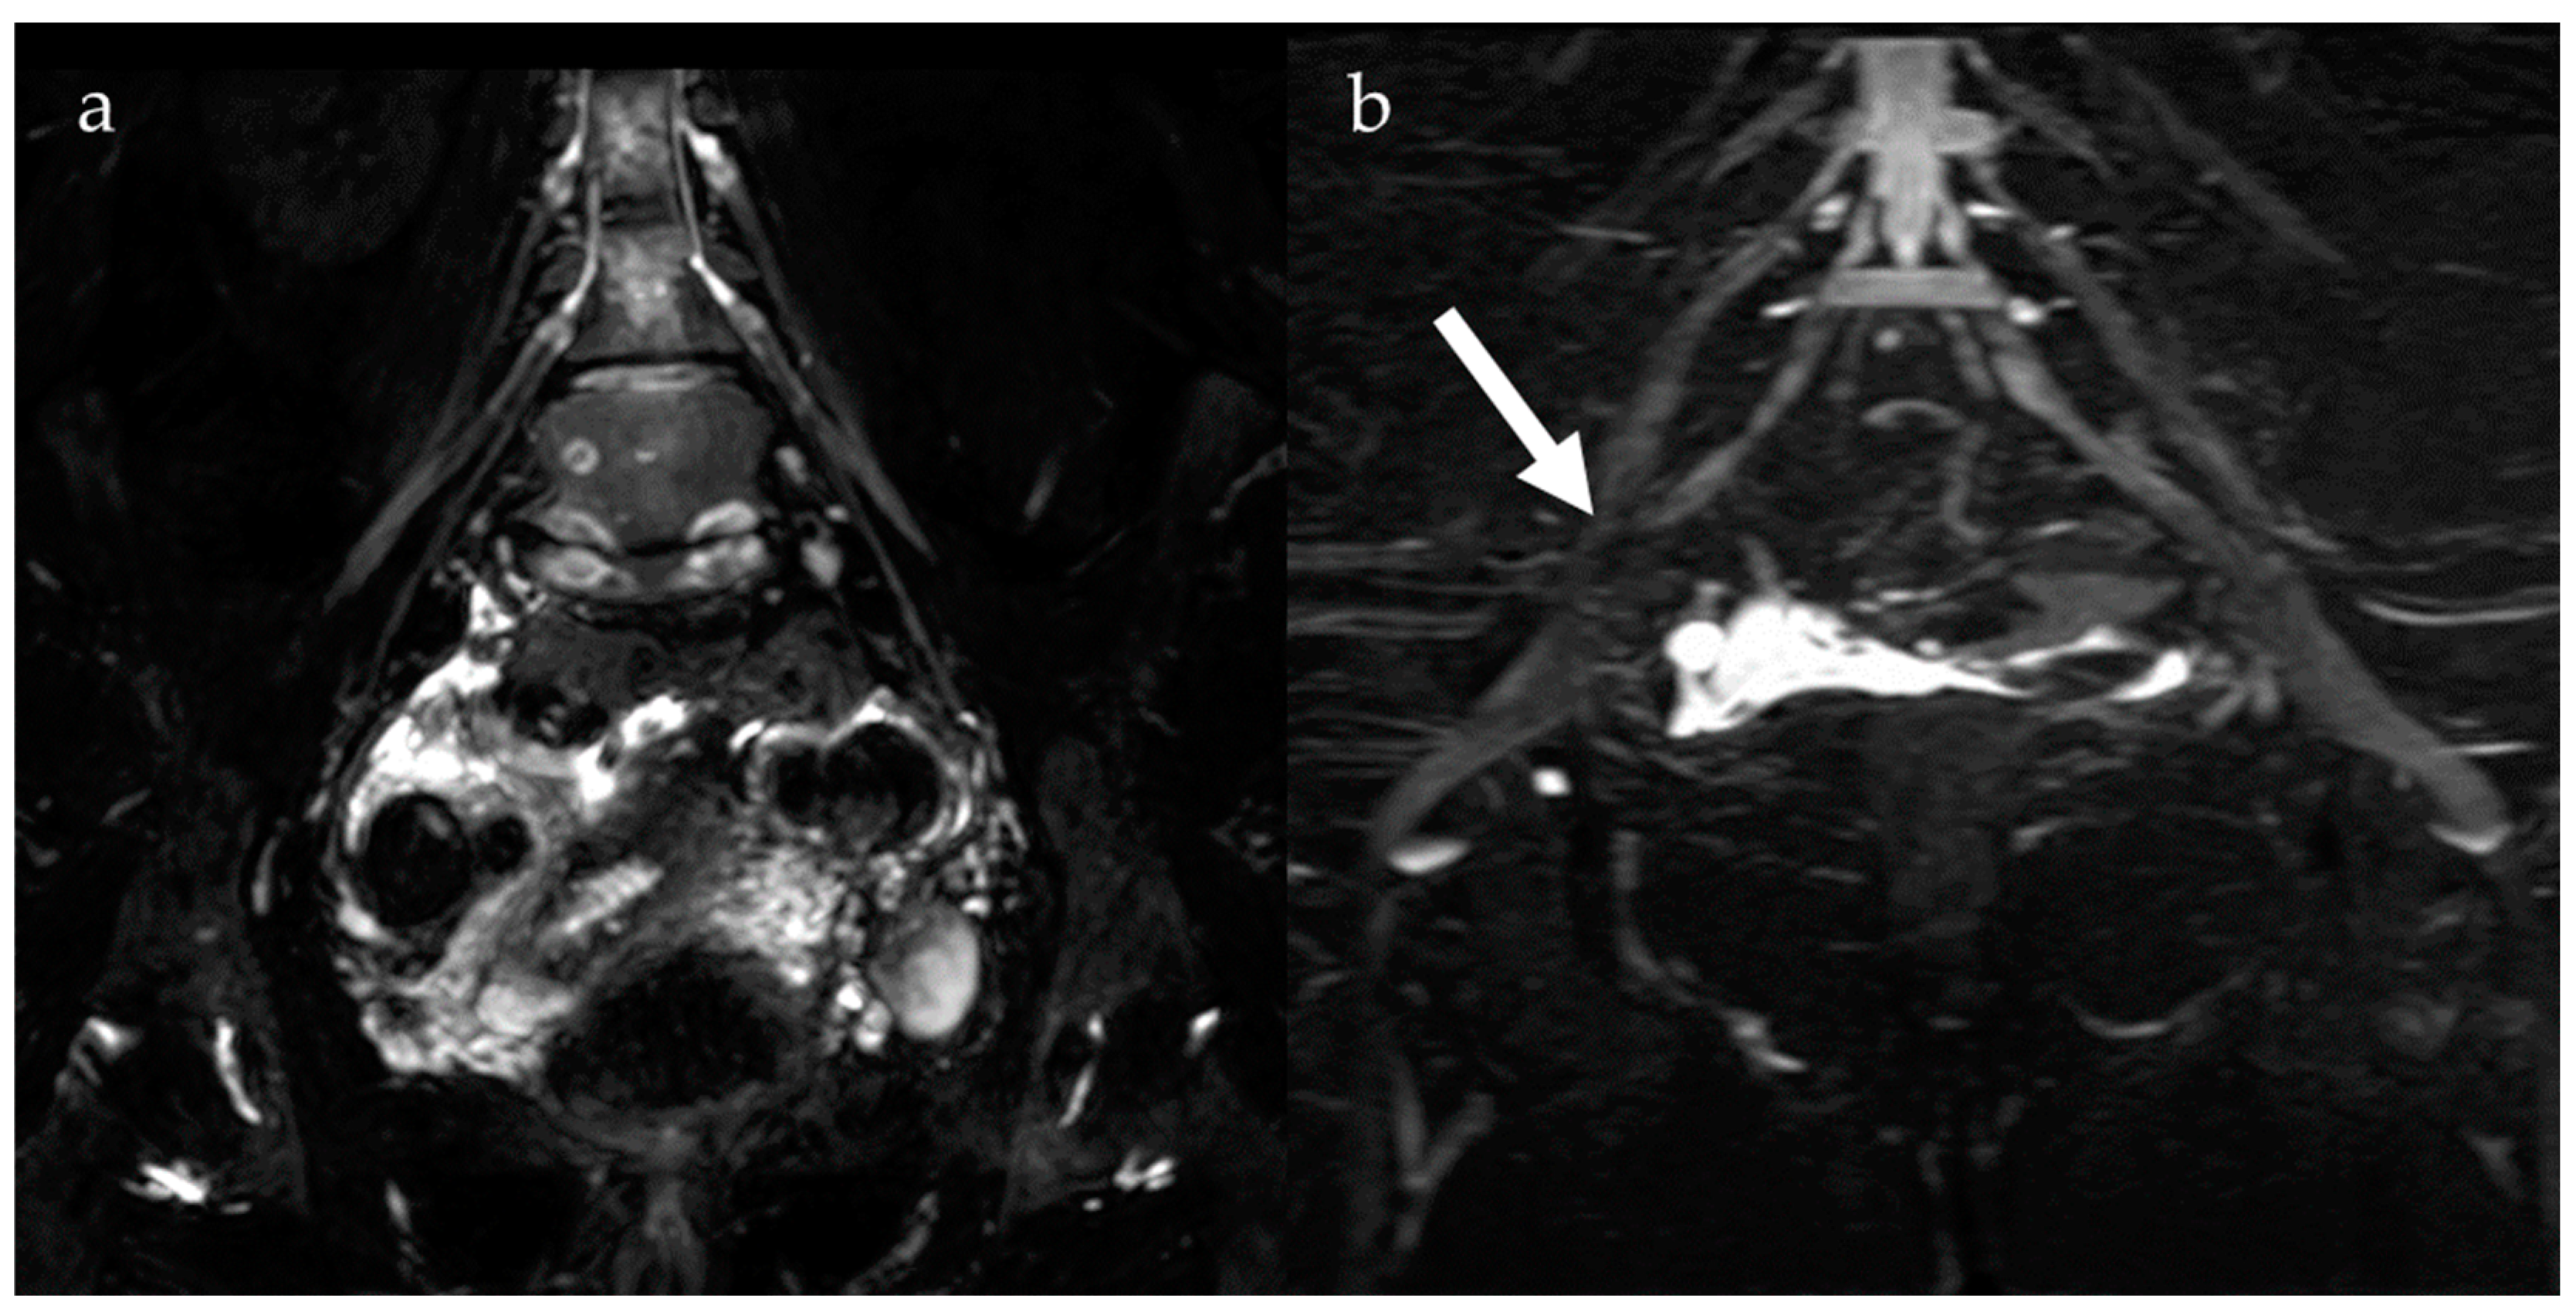

5. Susceptibility-Weighted Imaging

6. Magnetic Resonance Neurography and Diffusion Tensor Imaging